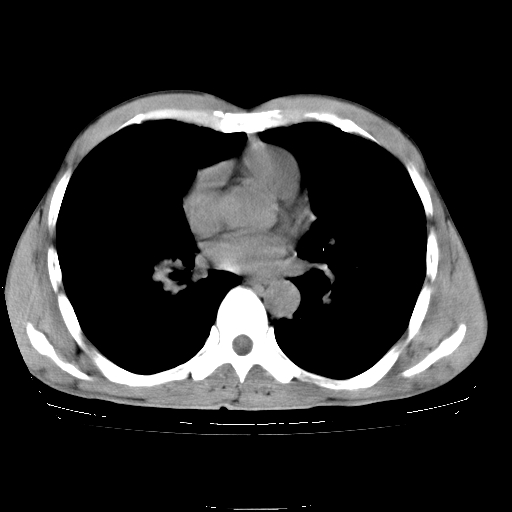

以下是引用yangyudong333在2008-4-29 5:38:00的发言:[br]比较典型的矽肺结节.支持[br]诊断依据:[br] 1.x线表现:[br] ①典型矽肺为多发直径 1~3mm 小结节,即矽结节,由胶原纤维和硅尘构成,可融合成团块,好发于上肺。[br] ②团块周围常有肺大泡。[br] ③胸内淋巴结增大、钙化。如肺门淋巴结呈蛋壳样钙化有助于与其他尘肺区别。[br] ④胸膜常广泛粘连、增厚。[br] 2.ct表现[br] ①两肺散在大小较为一致的小结节影,其密度较高,边界清楚。[br] ②小结节可融合为较大团块影,直径约 1cm ,甚至可达 10cm以上,易发生在上叶。[br] ③小结节周围常并有小叶中心气肿或弥漫性肺气肿。

以下是引用liuyue在2008-4-28 22:30:00的发言:[br]比较典型的矽肺结节.[br]请结合临床及化验除外矽肺合并肺结核之可能.